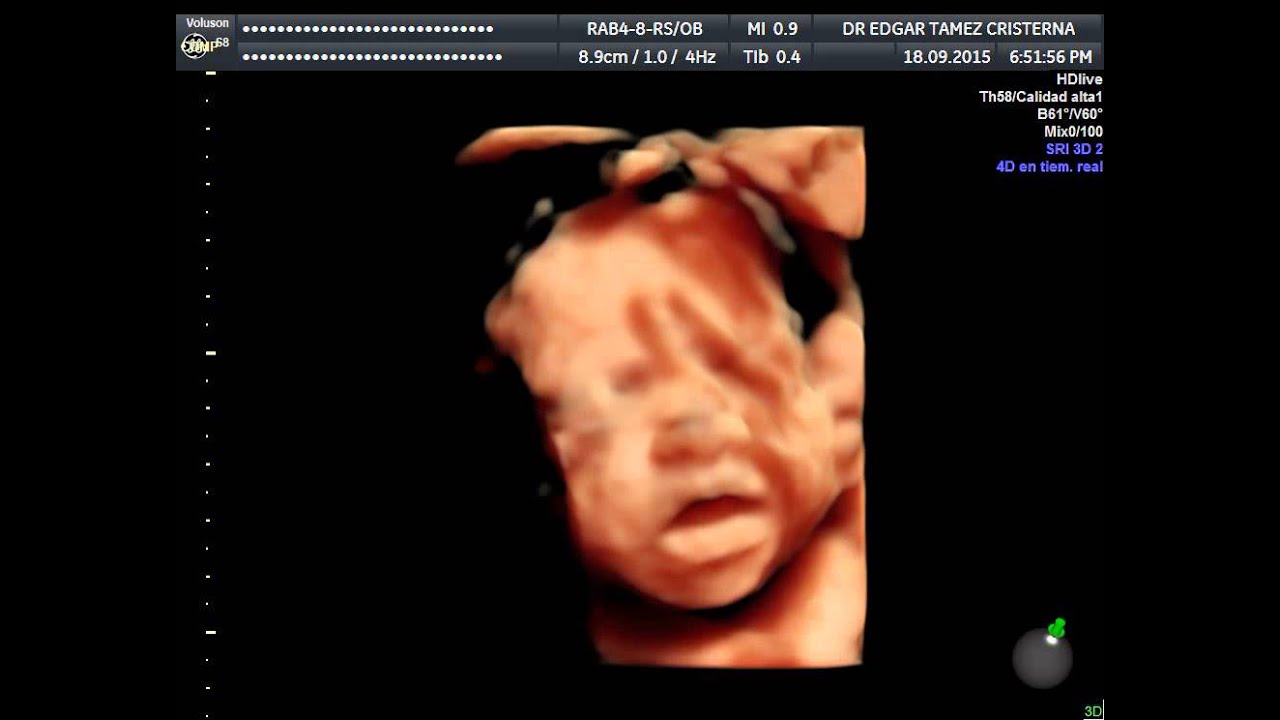

Aunque la ecografía 4D puede hacerse en cualquier momento de la gestación, se recomienda realizarla entre las semanas 26 y 30, ya que el feto estará suficientemente desarrollado como para observar mejor sus rasgos. La duración de la ecografía 4D es de 20-30 minutos, aproximadamente, y las imágenes obtenidas se entregan a los padres en.. Permite a los padres ver los gestos faciales del bebé en tiempo real. Su realización ayuda a detectar o descartar malformaciones y patologías genéticas del feto. Se puede analizar el crecimiento del feto, realizar medidas del feto más precisas y valorar así estado de las distintas estructuras del cuerpo. ¿Cuándo realizar la ecografía 4D?

La Prueba Ultrasonido 4D es útil para: Monitorear el desarrollo de un feto. Detectar posibles malformaciones en un bebé no nato. Observar los movimientos de un bebé dentro del vientre materno. Obtener información detallada de los órganos del feto así como del útero, placenta, ovarios y líquido amniótico. Conocer la posición del feto.. Diferencias entre Ultrasonidos 3D y 4D. La diferencia principal está en la manera en que se visualiza cada uno. En el 3D además de captar las expresiones del bebé, se pueden detectar el 85% de malformaciones morfológicas. Por otro lado, las ecografías 4D son la unión de varias imágenes tridimensionales que forman un vídeo, donde se.